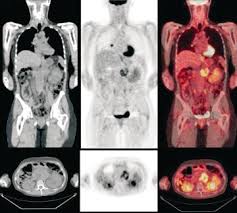

Certain chemotherapy and immunotherapy drugs can be especially effective in some tumor types but completely ineffective in others. The prognosis of pancreatic cancer (adenocarcinoma of the pancreas) is a very tough, though the survival rates have been incrementally improving particularly over the past ten to. Pancreatic cancer can be found in the exocrine glands, which produce enzymes that help you digest food. The symptoms may not be connected to pancreatic cancer but the indications do deserve a medical examination. The pancreas is situated behind the stomach, liver, gallbladder, spleen and small intestine, and is in front of the spine. Most people who develop pancreatic cancer are older than 45. Some patients describe pain starting in the middle abdomen and radiating into the back. The known major risk factors account for less than 40 percent of all cases. In the u.s., pancreatic cancer is 9th or 10th most commonly diagnosed cancer (depending on gender), but the fourth leading cause of cancer death in men and women. Pancreatic adenocarcinoma is the most common type of pancreatic cancer, accounting for about 95% of cancers of the pancreas. Not many people realize pancreatic cancer can be responsible for depression, even before you realize you have it. The risk for developing pancreatic cancer. The approach has pushed average survival to five years after diagnosis.